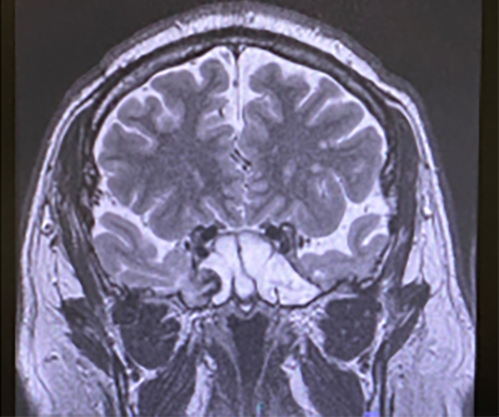

蝶形骨洞内に副鼻腔炎と脳瘤が存在。

出典

img

1: 著者提供